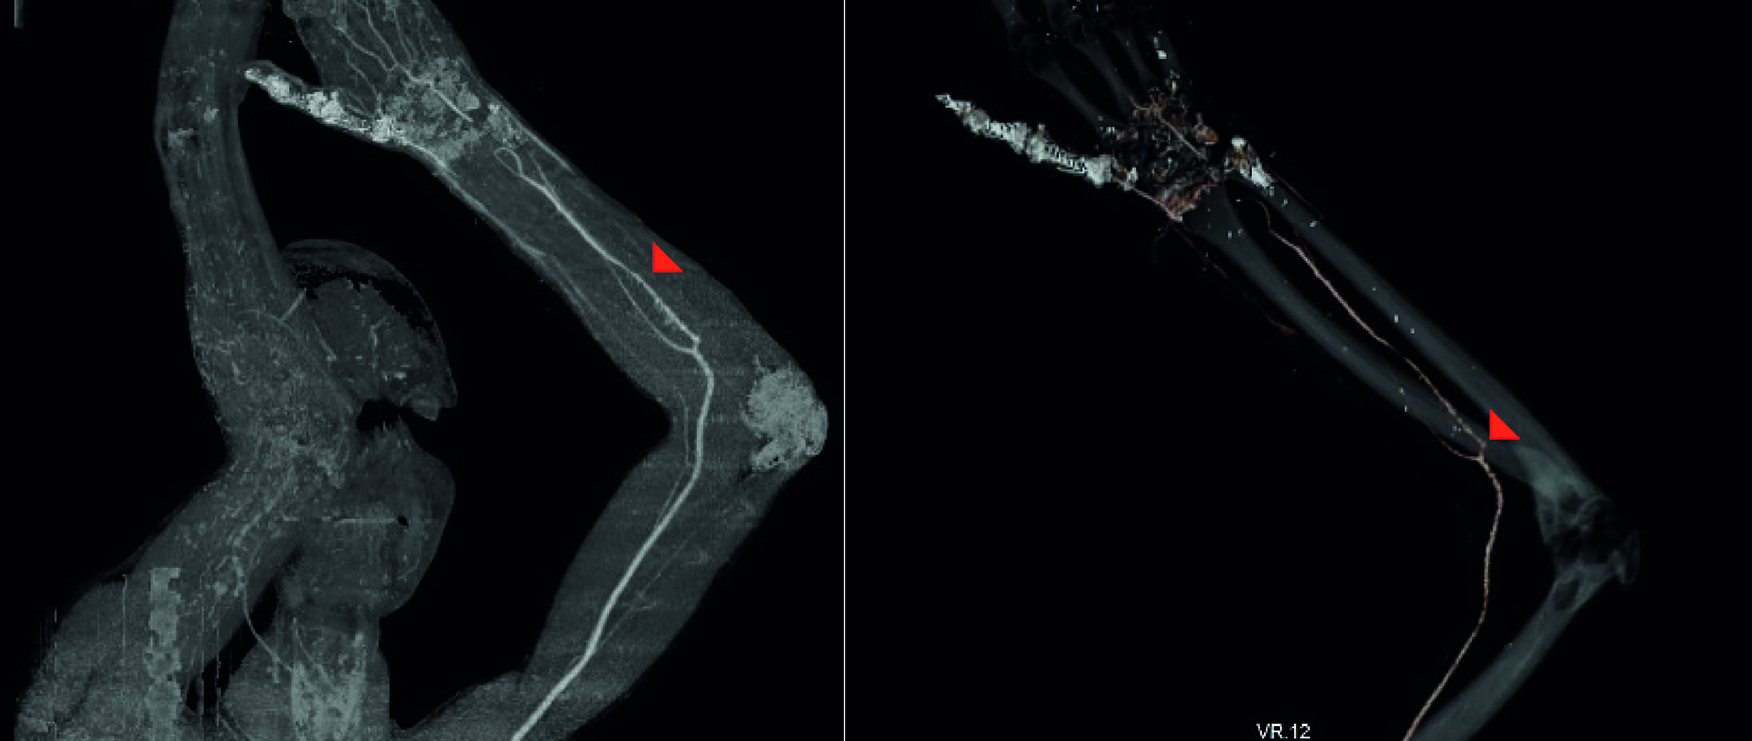

El estudio de imagen mostró una arteria mediana que se originaba como continuación de la arteria interósea anterior (Figura 2) y terminaba en la palma con un arco palmar superficial incompleto (Figura 3). Se infirió que la perfusión conservada de la mano (Figura 4) sin necesidad de anastomosis de la arteria ulnar o radial fue secundaria a la presencia de la variante anatómica diagnosticada en la tomografía (Figura 5). No hubo reacción adversa al contraste.

Figura2 Masculino de 33 años. Sección completa de las arterias radial y ulnar. A. La flecha roja indica la arteria mediana. B. La flecha roja indica el origen de la arteria mediana como continuación de la arteria interósea anterior. Angiotomografía. Inyección de Ioversol. 100 mL. 3 segundos.